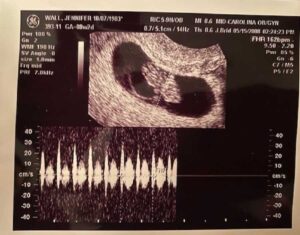

Things were fine, for about a week. I had another OB appointment and they performed an ultrasound to check on the baby and to detect the heartbeat for the first time. I remember the sonographer being eerily quiet. I knew something was wrong because not only did we not hear a heartbeat, but she wasn’t saying a word to us. I knew enough to know they weren’t allowed to disclose any information – that was reserved for the doctors. She said that the doctor would be with us in a few minutes and we were ushered to a private office to wait.

The doctor on call came in and said that with the size of the baby, and the gestational age, they should have seen a heartbeat, but there wasn’t one. He also informed me that I have a bicornuate uterus. When I was being formed inside my mother, my uterus didn’t form correctly and it is shaped like a heart. This would explain part of the reason it took two years to conceive!

The doctor looked at the ultrasound and consulted with another doctor. They agreed they were 99% sure I would miscarry the baby. He was very kind, but to the point. The doctor scheduled a D&C procedure for three days later. I remember feeling my heartbreak as they escorted us out a side door so that I didn’t have to pass the expecting mothers in the waiting room. I think this was for their sake as well as mine.

I went back with the sonographer alone and she told me she wanted to do an ultrasound just to make sure. I lay back while she prepared the machines. I remember the cold gel against my lower stomach and I remember not wanting to look up at the screen. I remember her sweet but sad smile. Surely this woman had seen many happy and many sad times in this room. I didn’t want to see my empty womb where my baby used to be. I was looking up at the ceiling, impatiently waiting until I could just go home. The sonographer whispered under her breath, ‘Thank you, Jesus.’ I was confused and looked at her in time to see her wiping at her face. I asked her what she was talking about and she turned on her machine, positioned the doppler on my belly, and I heard my baby’s heart beating. I was in complete awe. My baby was alive. I was flabbergasted. There was so much blood, I was sure I lost the baby. She pointed up to scripture that she had hanging in the office that said, ‘With man things are impossible, but with God all things are possible.’

The doctor came in to see us and stared down at the ultrasound pictures for several minutes before looking up at us in confusion. He said, ‘There is no explainable way your baby survived.’ I said, ‘I have an explanation…God did it.’ My faith told me all I needed to know. If I had gone for the D&C procedure that was scheduled a few days before, I would have surely lost the baby. My bicornuate uterus, along with a subchorionic hemorrhage, caused a lot of bleeding. The baby had less space than average so I felt everything a lot earlier than most.